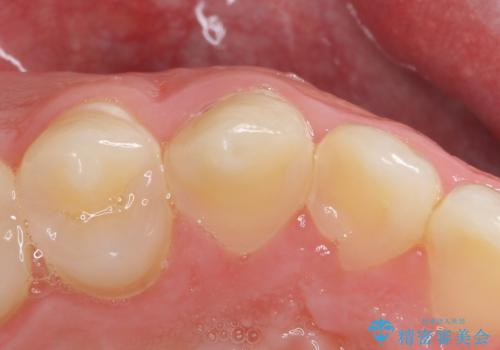

全体的に歯の脱灰が目立っており、右上の犬歯のみ状態が悪く穴が開いてしまっていました。

審美的にも優れるセラミッククラウンで修復し、他の歯も同じ状態になってしまわないよう歯磨き指導をさせていただきました。